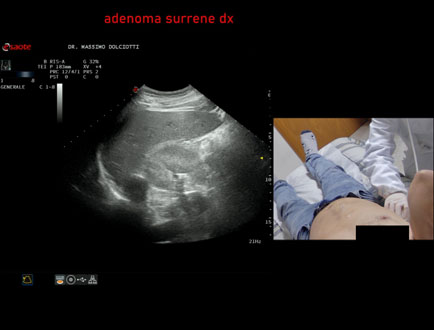

Data inserimento: 02/04/2021

Ecografia del: 01/04/2021

Strumento: Esaote MyLab Twice

Sonda: Convex Multifrequenza 1-8 MHz

Età Paziente: F 76 anni

Motivazione dell'esame: follow up di adenoma surrenalico destro.

Commento all'esame: le immagini ed il video documentano formazione ipoecogena, in sede surrenalica destra, delle dimensioni massime documentate di 33,1 x 21,5 mm, da ricondurre ad adenoma surrenalico.

Conclusioni: adenoma surrenalico destro (right adrenal adenoma).